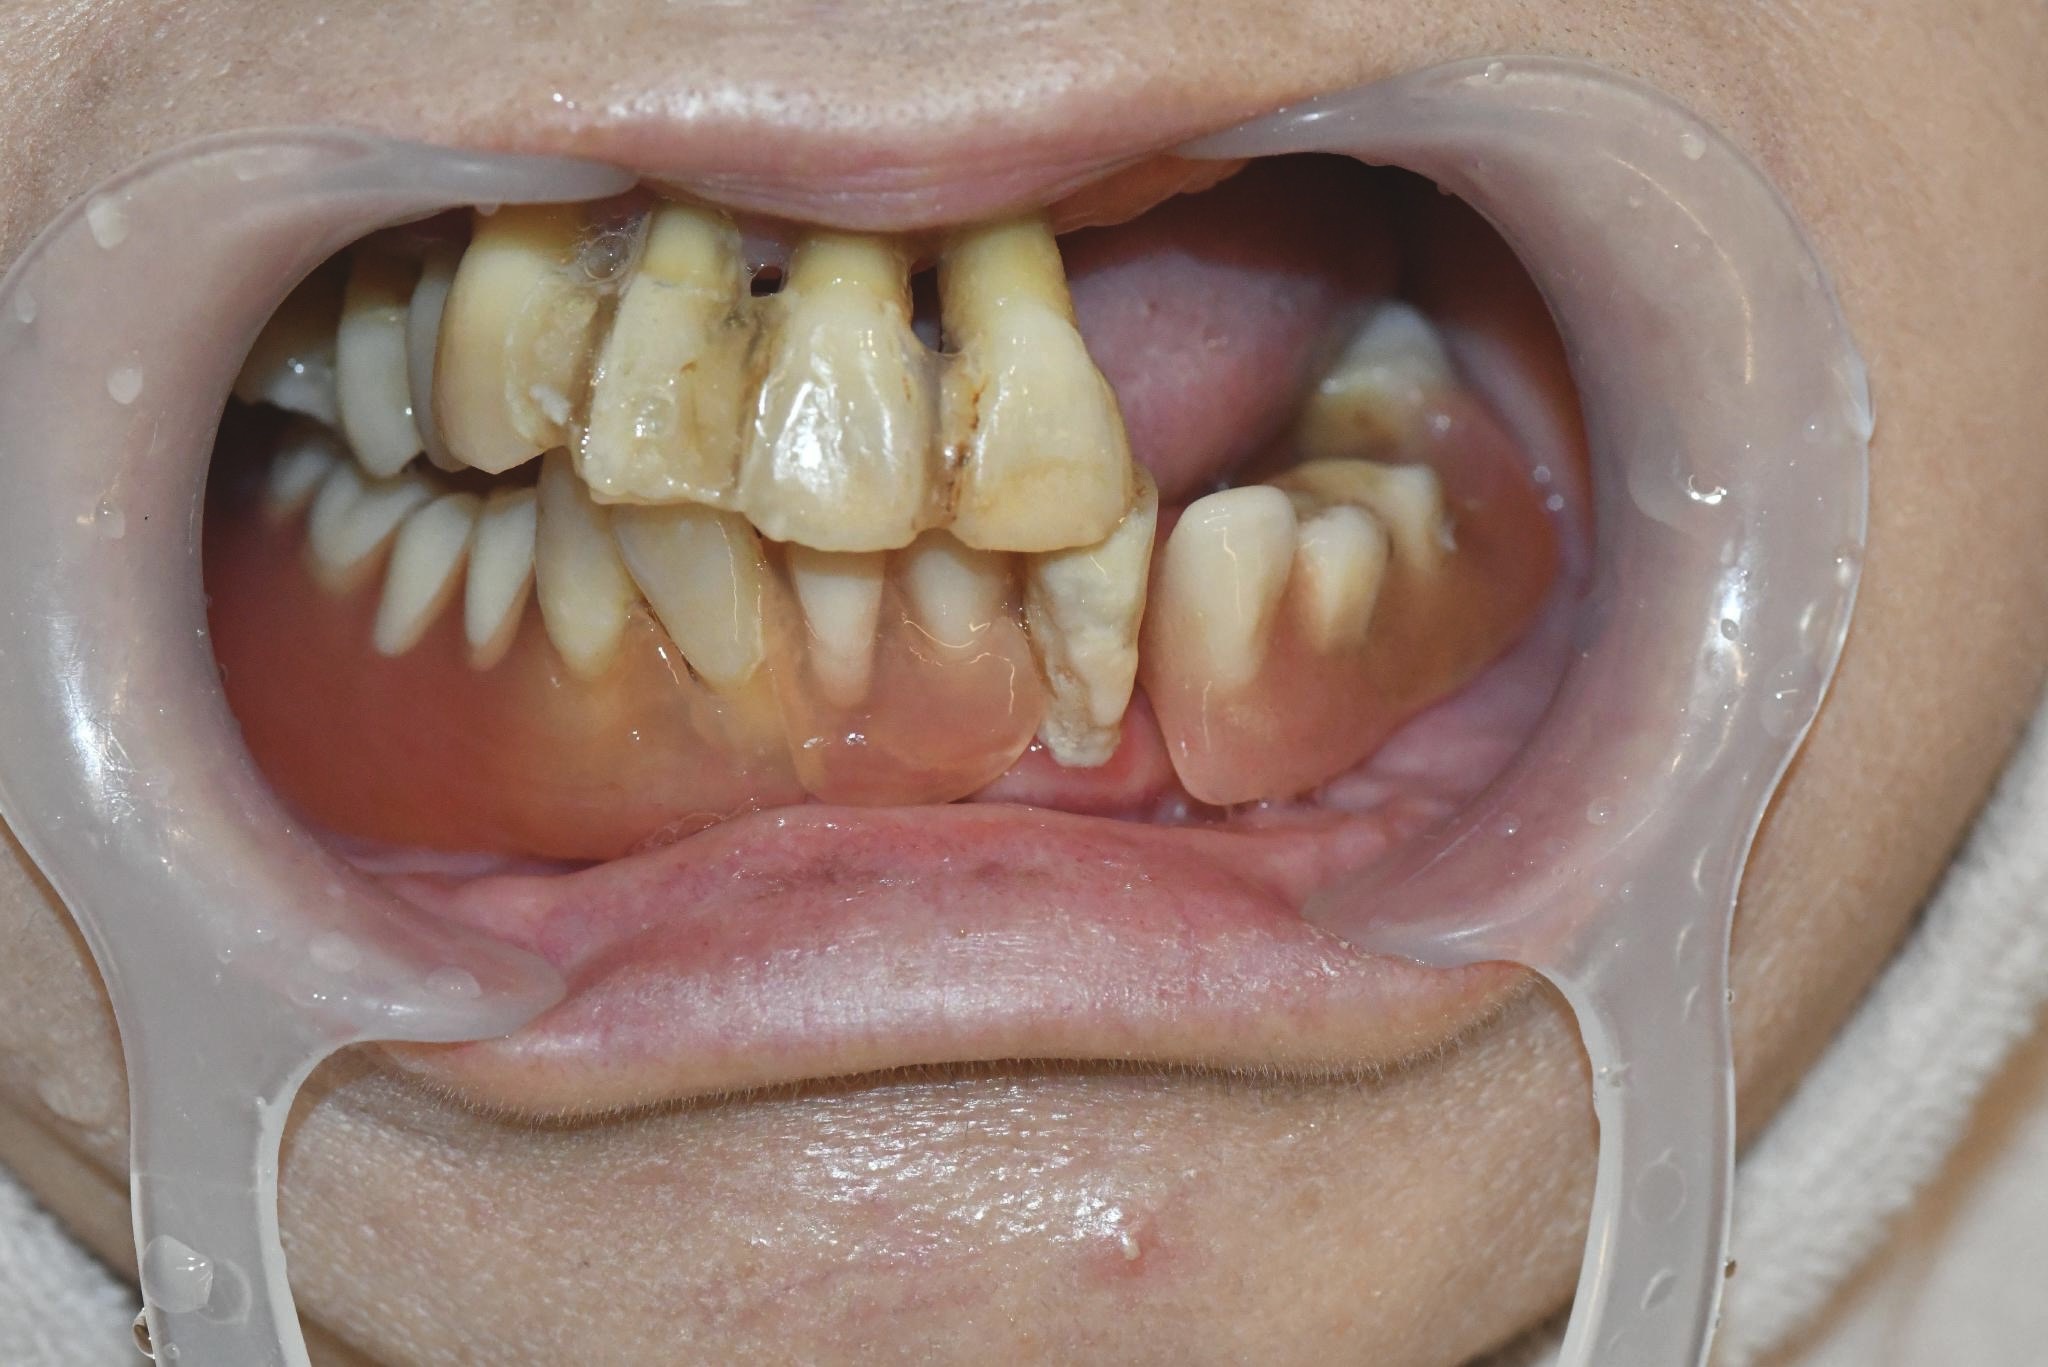

術前

食事をしてもうめく噛めないため、食べるたびに不便さを感じていました。見た目も気になり、人前で口元を見せることに抵抗がありました。6年前に他院で作ってもらった入れ歯が合わず、解決しない状況が続いていました。